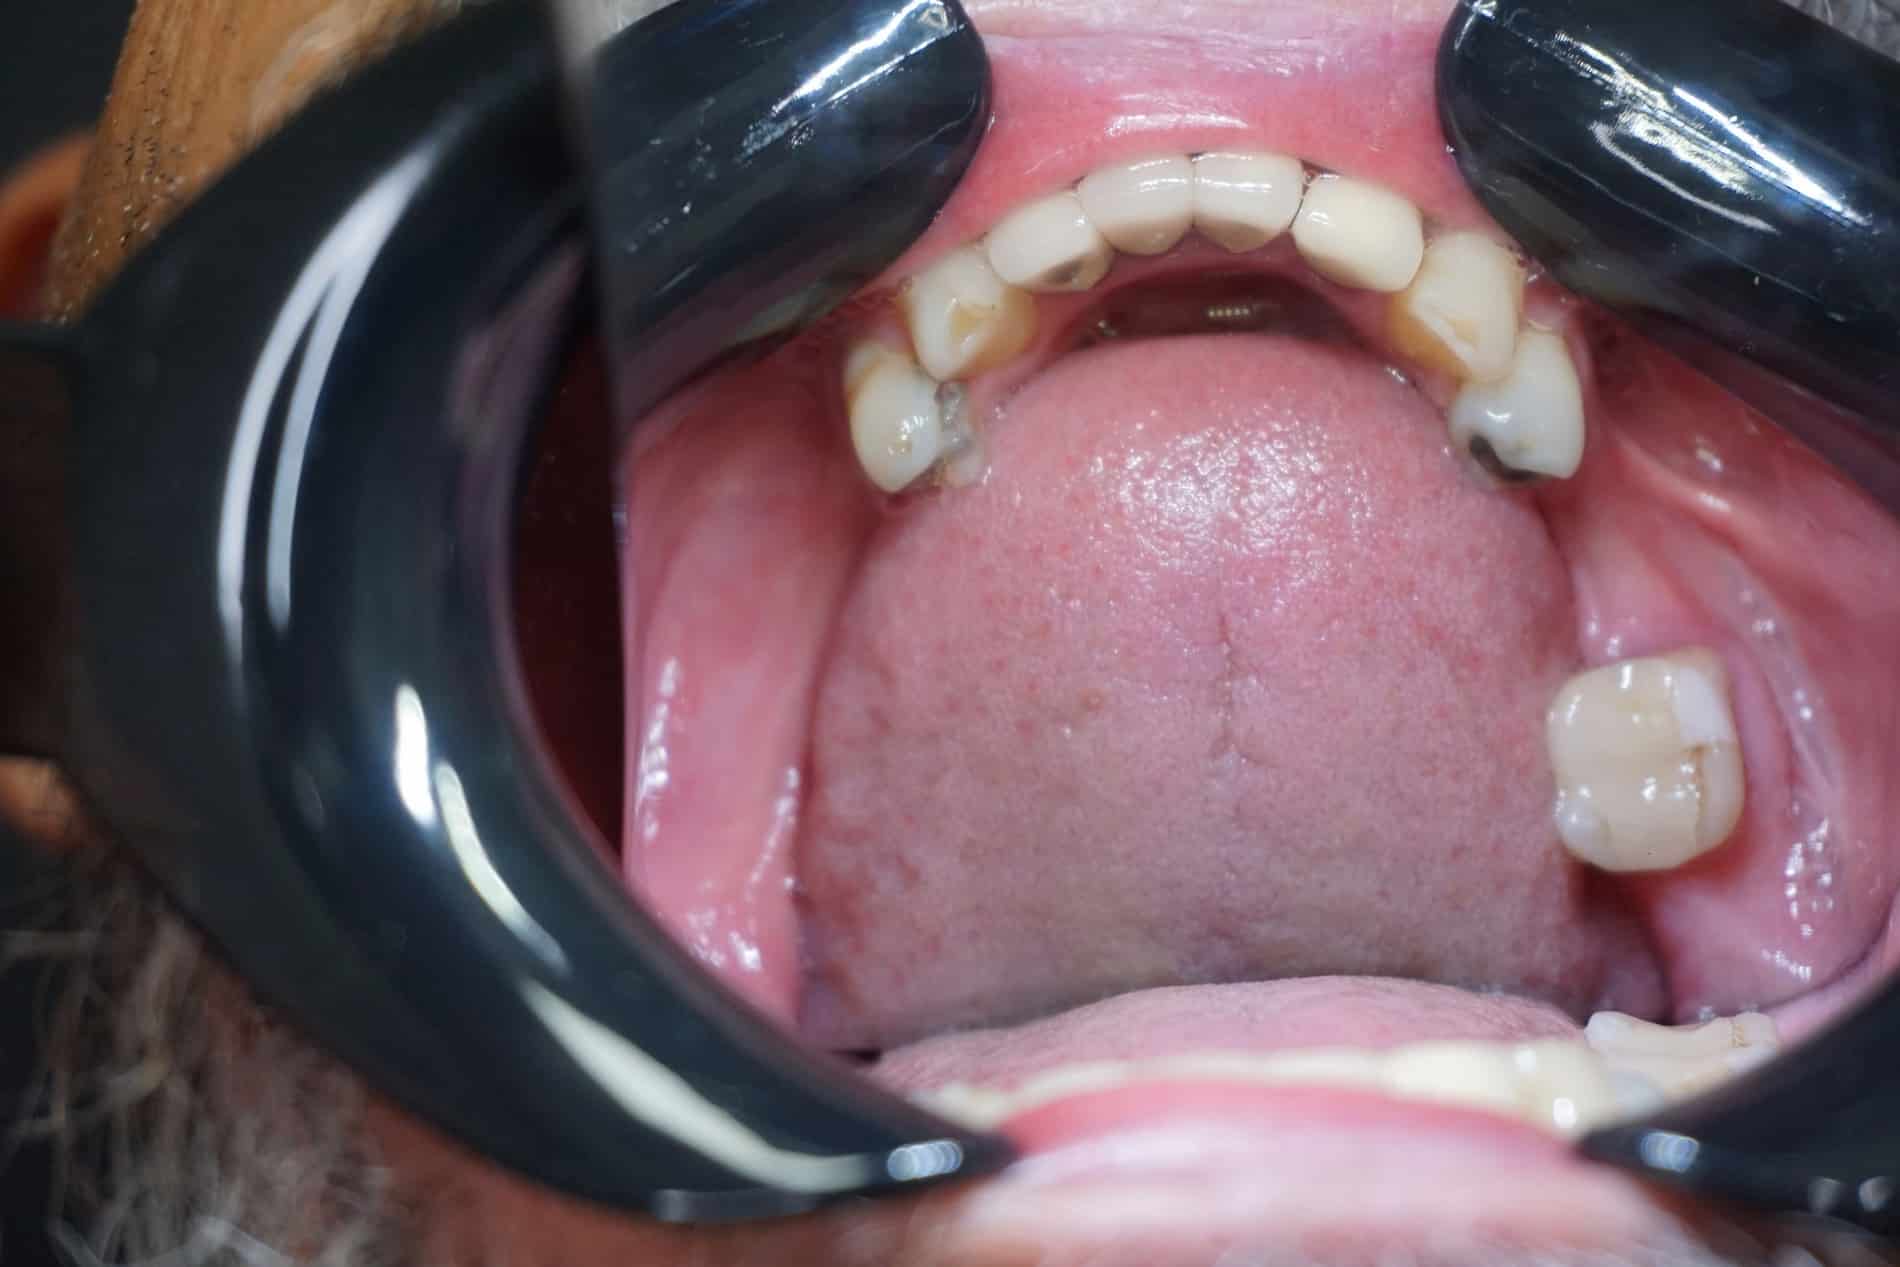

Johns smile before dental impants with Dr. Seale in Rincon GA

Before Full Mouth Restoration

Johns mouth before a implant bridge in Rincon GA

Before